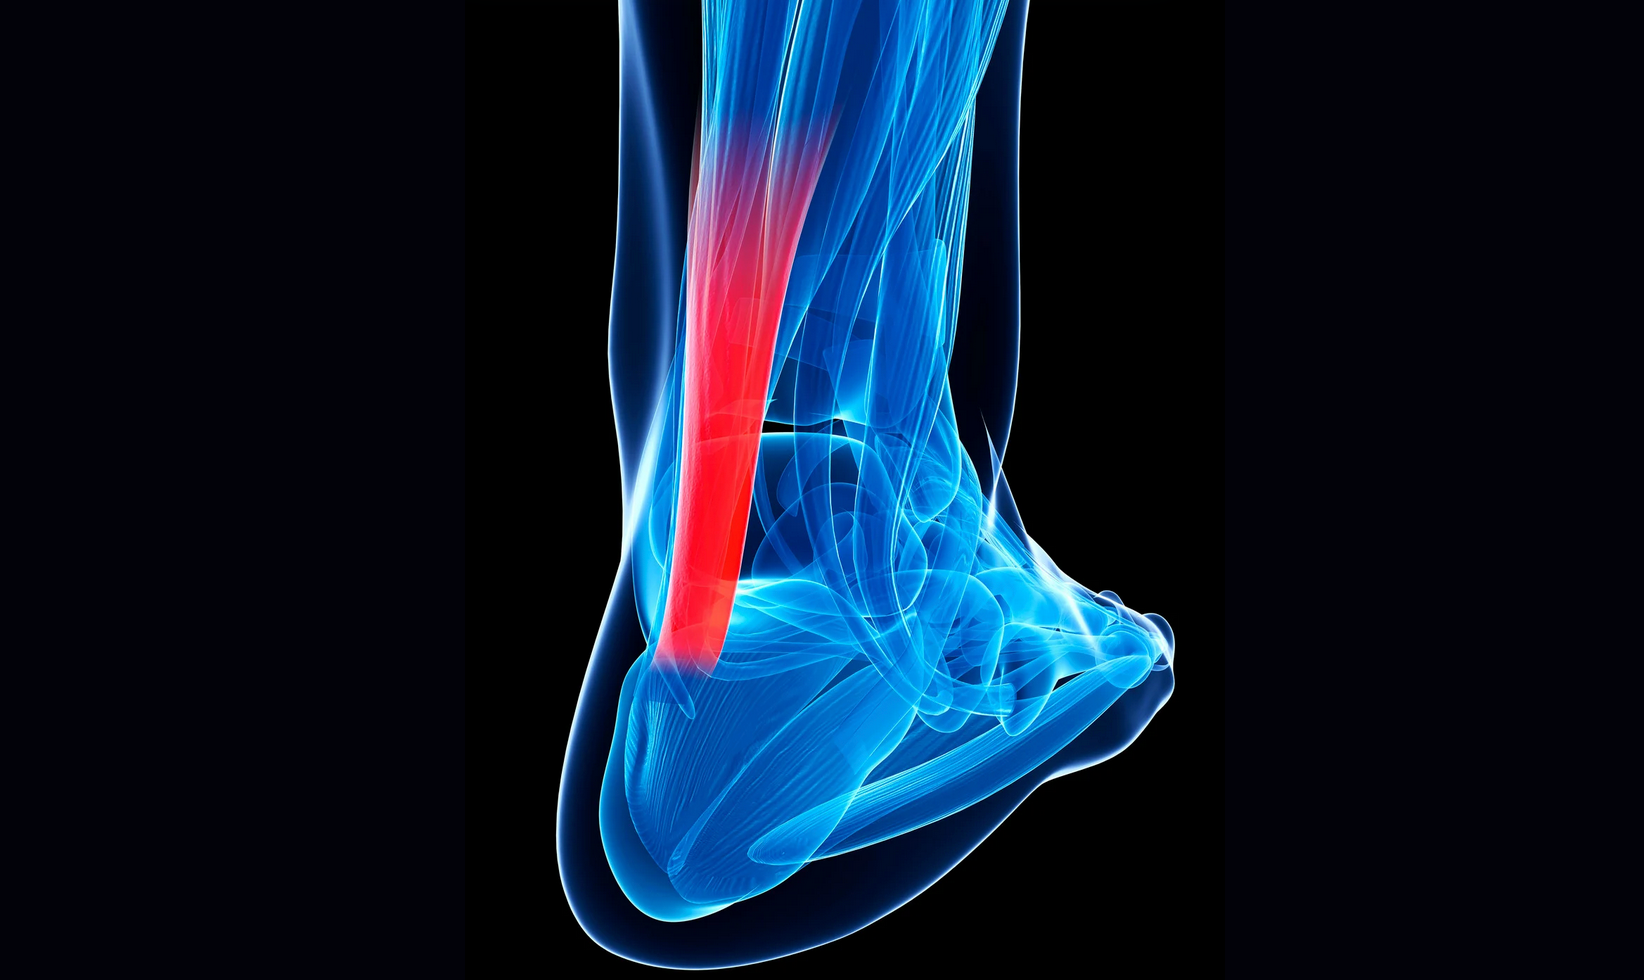

- -Inflamación neurógena (propia del nervio): a través de los nociceptores se genera en sentido eferente una vasoactividad y la consecuente vasodilatación, edema, implicación del sistema de defensa; mastocitos, leucocitos, etc.